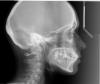

Ayza1 Опубликовано 2 марта, 2013 Поделиться Опубликовано 2 марта, 2013 Это снова я. На старый логин не разрешают больше добавлять картинки.Я нашла старые исследования. Может будет полезно. КТ ВЧ 29.10.2010 http://webfile.ru/6408333И еще снимок с той же датой. 29.10.2010.Брекеты я еще не носила. Ссылка на комментарий

Skip Опубликовано 2 марта, 2013 Поделиться Опубликовано 2 марта, 2013 Добрый вечер, Люба! Это лечится, разумеется.Спасибо за ТРГ, я чуть позже проанализирую. Хотелось бы увидеть ТРГ и на сегодняшний день, чтобы посмотреть ДО и ПОСЛЕ. Также интересует ещё две проекции, но здесь я Вас не могу направить, т.к. провожу это обследование только своим пациентам. Если хотите сделать эти снимки на собственном энтузиазме и показать их нам здесь, то я Вам могу подсказать, где их можно будет сделать в Москве. Ссылка на комментарий

Skip Опубликовано 2 марта, 2013 Поделиться Опубликовано 2 марта, 2013 Сделать нужно три проекции: 1. Боковая ТРГ2. Прямая ТРГ (между зубов за клыками установить одноразовый слюноотсос)3. Подбородочно-теменная проекция (SMV) http://www.picasso-diagnostic.ru/ м.Рижская (пр-т Мира) ул. Гиляровского, д. 65, подъезд 7, этаж 4, Рентгенолог Астафуров Александр 8-968-736-17-20. Он всё знает, как правильно сделать. Только скажите еще, снимать ли мне брекеты сейчас? Давайте сначала оценим масштаб, ок? P.S. Фото можно загружать на http://pixs.ru/ , а сюда потом ссылку вставлять с кодом для форумов. Ссылка на комментарий

Ayza Опубликовано 5 марта, 2013 Автор Поделиться Опубликовано 5 марта, 2013 (изменено) http://i5.pixs.ru/thumbs/6/2/0/6648BOKjpg_9687482_7300620.jpg http://i5.pixs.ru/thumbs/6/6/0/6648BRAKjp_8295761_7300660.jpg http://i5.pixs.ru/thumbs/6/6/3/6648PRjpg_1216029_7300663.jpg http://i5.pixs.ru/thumbs/6/6/4/6648SMV1jp_7786998_7300664.jpg http://i5.pixs.ru/thumbs/6/6/8/6648SMVjpg_6113146_7300668.jpg Слюноотсос, оказывается, нужно было принести с собой. Рентгенолог сказал, что давно уже делает без него, врачей устраивает. Изменено 5 марта, 2013 пользователем Ayza Ссылка на комментарий

Skip Опубликовано 5 марта, 2013 Поделиться Опубликовано 5 марта, 2013 Добрый вечер! Всё, как я и предполагал. У Вас изначально есть одна проблема, а именно то, что верхняя челюсть находится в достаточно выраженной ретропозиции, другими словами расположена в черепе кзади. И, в то же время, размер верхней челюсти (вч) в норме. Эта ретропозиция вч компенсировалась протрузией передних зубов, что обеспечивало адекватную поддержку верхней губы и Ваше милое личико выглядело сбалансированным ДО ЛЕЧЕНИЯ. Это анализ ТРГ до лечения. Обратите внимание на самую глубокую точку вч, называемую А-Point и расстояние до передней дуги (зелёная): http://i5.pixs.ru/storage/7/4/3/analiz7jpg_9837587_7304743.jpg А это ТРГ после проведённого лечения. Расстояние A-Point до передней дуги увеличилось почти вдвое! http://i5.pixs.ru/storage/7/4/6/analizposl_8117403_7304746.jpg Мы ортодонты часто проводим такой камуфляж, меняя положение точки А. НО, такие изменения проводятся только в том случае, когда верхняя челюсть увеличена в размере. В Вашем же случае, размер вч нейтральный, а учитывая её ретропозицию, любое изменение положения А-Point, в этом случае, я называю "поцелуем смерти". А по сути, произошло укорочение вч, изменение положения верхних резцов, потеря поддержки верхней губы. Те изменения лица, которые мы сейчас видим, обусловлены не удалением 8-ок, разумеется. По анализу ТРГ видно, что изменились и вертикальные пропорции лица (обратите внимание на две маленькие чёрточки в самом низу ТРГ красного цвета) До и После, так как произошла ротация нижней челюсти и углубление прикуса. Всё это привело к укорочению физиологической длины мимических мышц лица. Когда мышца излишне напрягается и укорачивается, её веретенца посылают в мозг соответствующие импульсы. Мозг в ответ дает команду сокращаться мышце-антагонисту. Перенапряженная мышца постепенно теряет тонус и, при условии большой продолжительности такого состояния, постепенно слабеет. Вскоре ее сила становится меньше силы мышцы-антагониста, она не может ей противодействовать и становится еще короче. Развивается диспропорция размеров мышц со всеми вытекающими. Если она не растягивается до необходимой длины в расслабленном состоянии, то постепенно теряет эластичность, эластичные волокна в ней заменяются неэластичными и всё это находит отражение в лице. http://i5.pixs.ru/storage/7/5/1/Cosmeticim_4323850_7304751.jpg У меня к Вам вопрос, какие цели Вы преследовали, начав ортодонтическое лечение? Всё это можно исправить или методами черепно-лицевой ортопедии или хирургией. Первый вариант предпочтительней, но потребует времени и определённых знаний и усилий от доктора. 7 Ссылка на комментарий